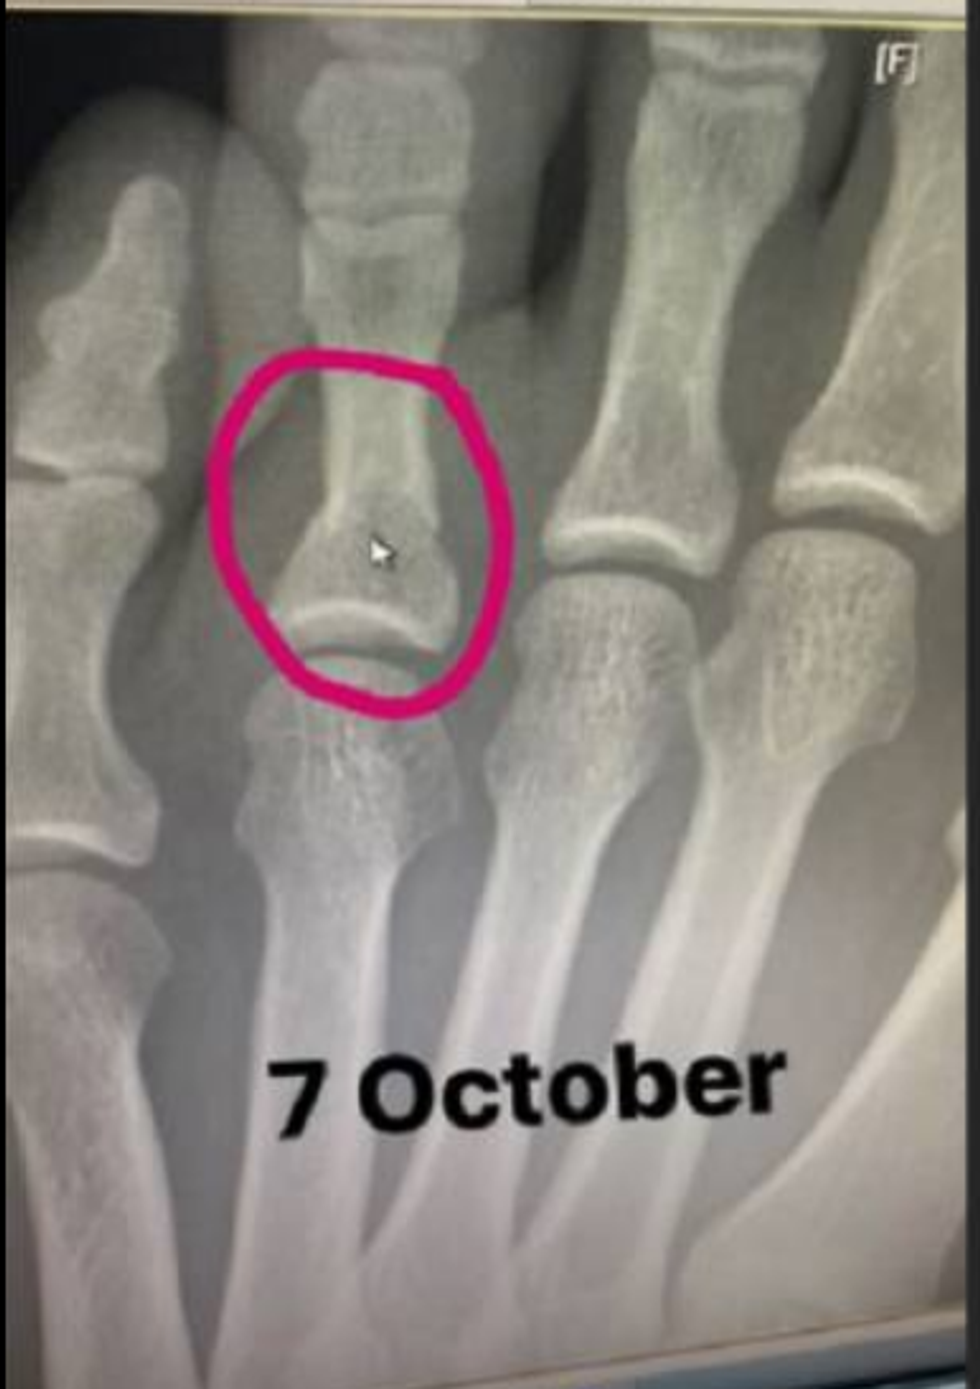

Në konferencën për shtyp pas meçit, Dana White konfirmoi se luftëtari i njohur kishte luftuar me disa fraktura në këmbën e tij të majtë.

“Ne ishim me fat që e pamë atë duke luftuar sonte. Khabib është në spital, ai pati frakturë në këmbë tri javë më parë. Khabib theu dy gishta dhe një kockë në këmbë, por ai nuk i tregoi askujt. Ai është një nga njerëzit më të fortë në planet dhe luftëtari më i mirë në botë”, kishte thënë White pas meçit.

Vetë Khabib ka treguar fotot e lëndimeve që i kishte përmes llogarisë së tij në Instagram.

Luftëtari nga Dagestani ngarkoi një foto të një radiografie të 7 tetorit të kaluar në të cilën shihet një frakturë në njërin nga gishtat e këmbës dhe, menjëherë më pas, ngarkoi një foto tjetër në të cilën ai gisht ishte e mavijosur.